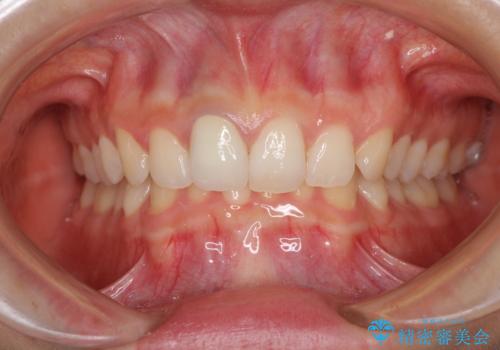

あっという間に気になっていた変色が解決し、早く治療を始めれば良かったとおっしゃっていました。

オーダーメイドタイプのクラウンを選択いただいたので、まるで天然の歯と見間違うほど自然に仕上がり、患者様には大変満足していただきました。